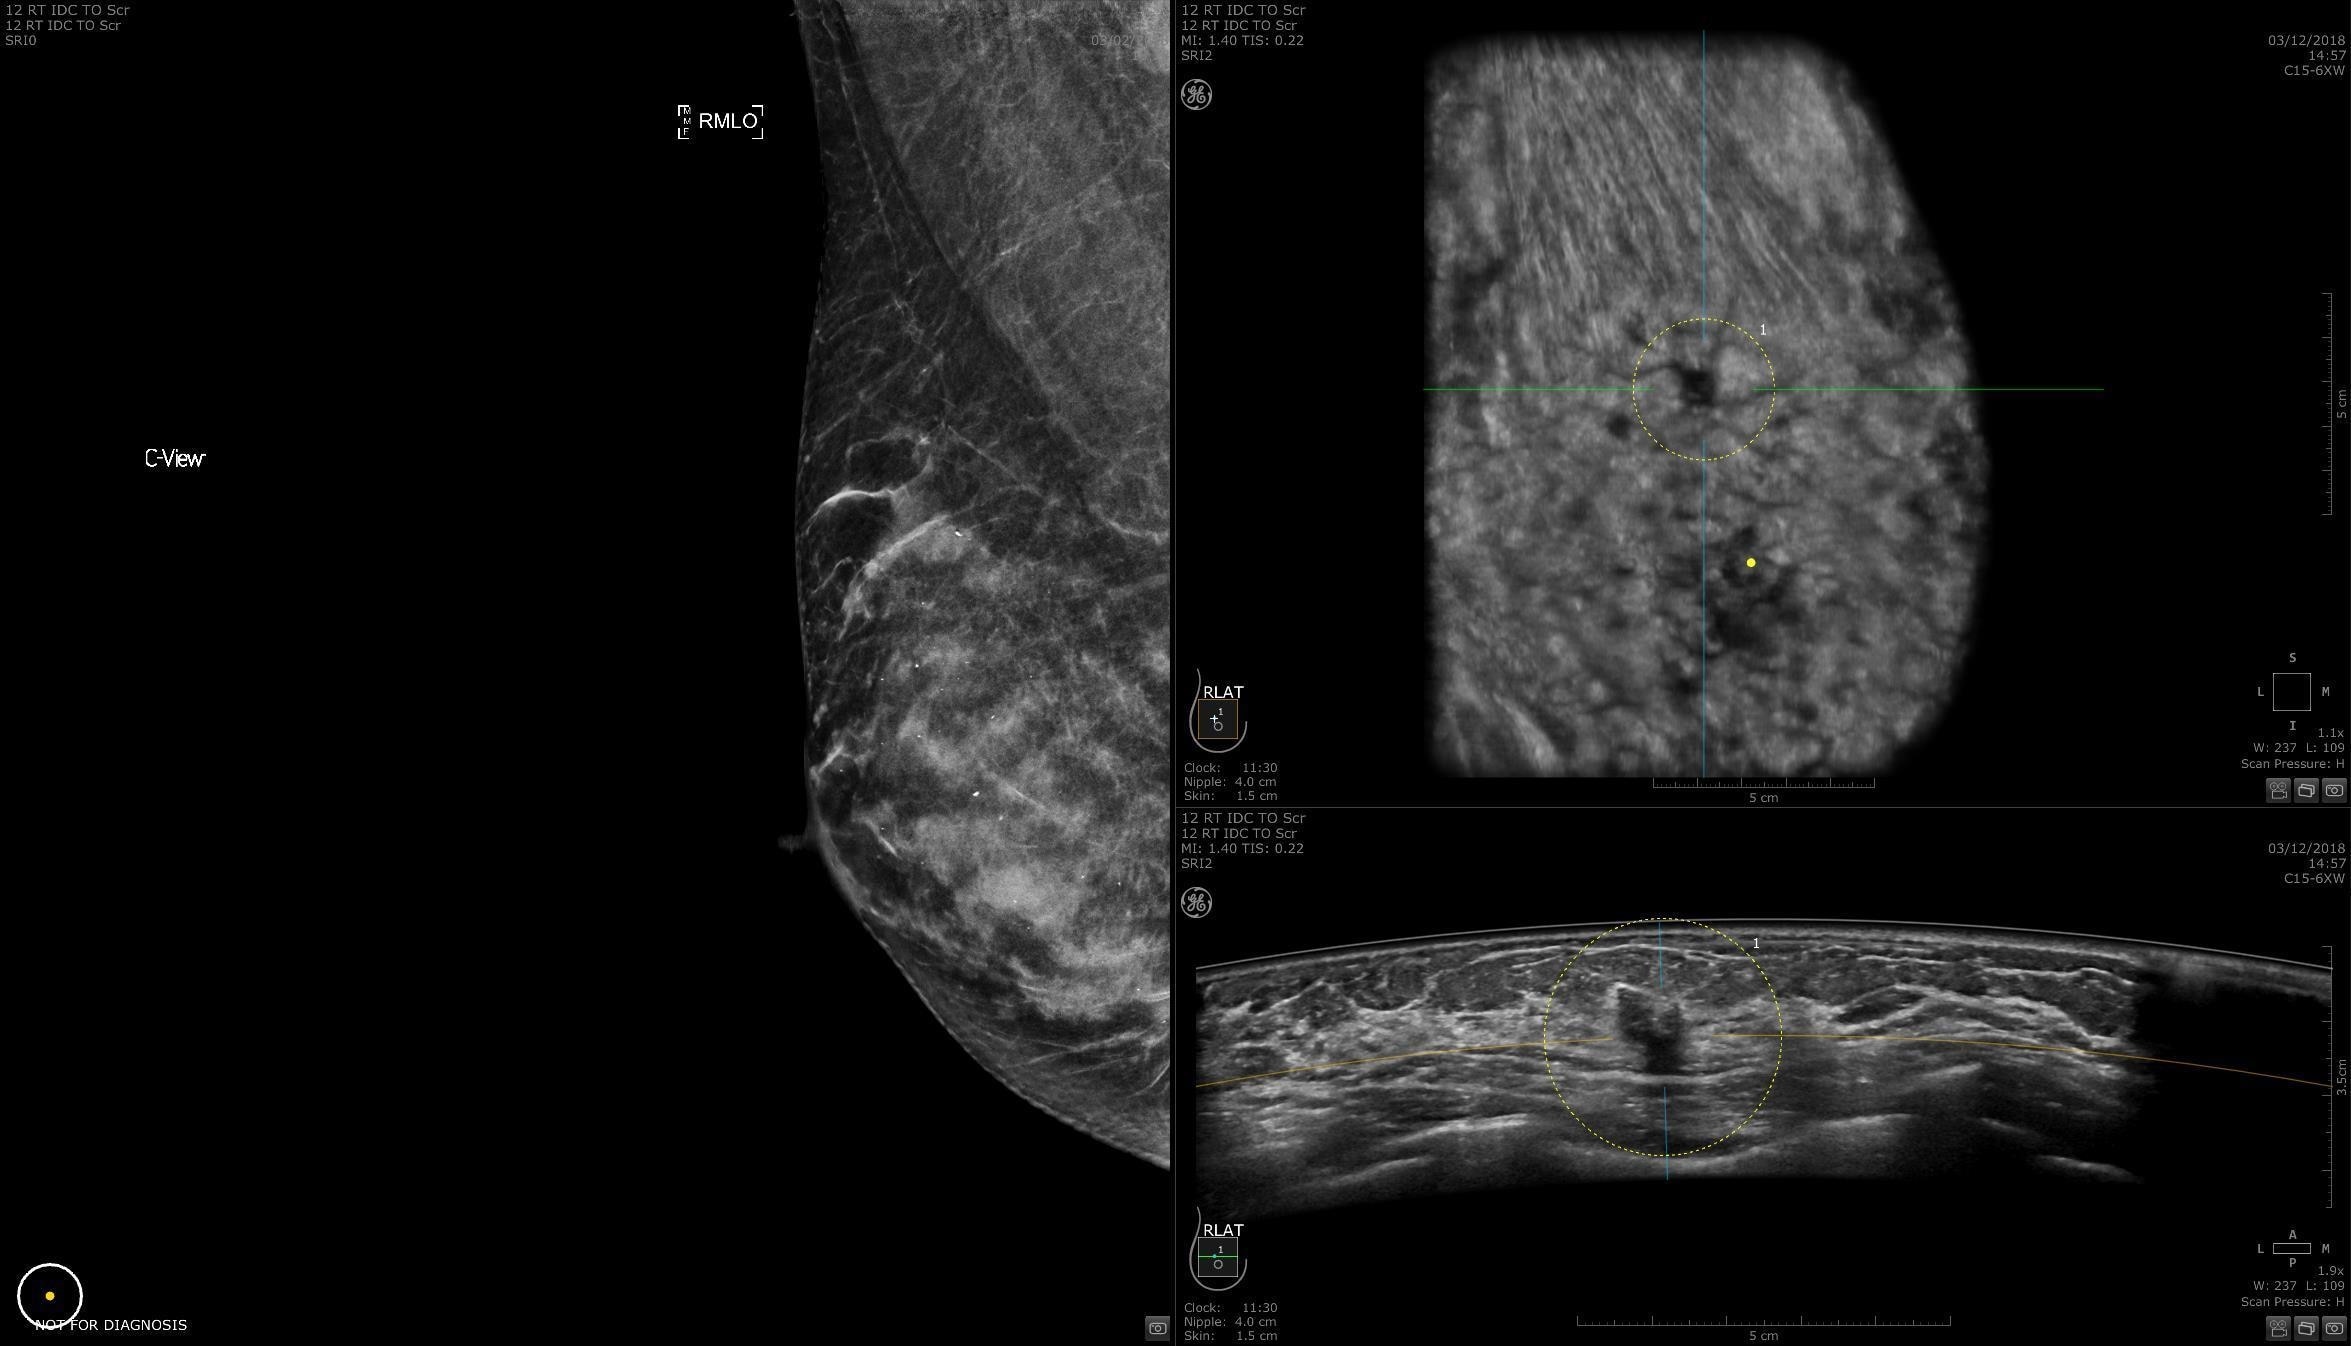

Dense breast tissue and cancer appear white on a mammogram, potentially camouflaging small cancers. Invenia ABUS 2.0, is specifically designed to help clinicians find cancers that may be hidden on mammography1,2.

SCREENING

The power of early cancer detection

Supplemental screening with Invenia ABUS 2.0 transforms breast care from reactive to proactive. When used in addition to mammography, Invenia ABUS 2.0 can improve breast cancer detection by 55 percent over mammography alone5. Women whose breast cancer is detected at an early stage have a 90% or higher survival rate6.